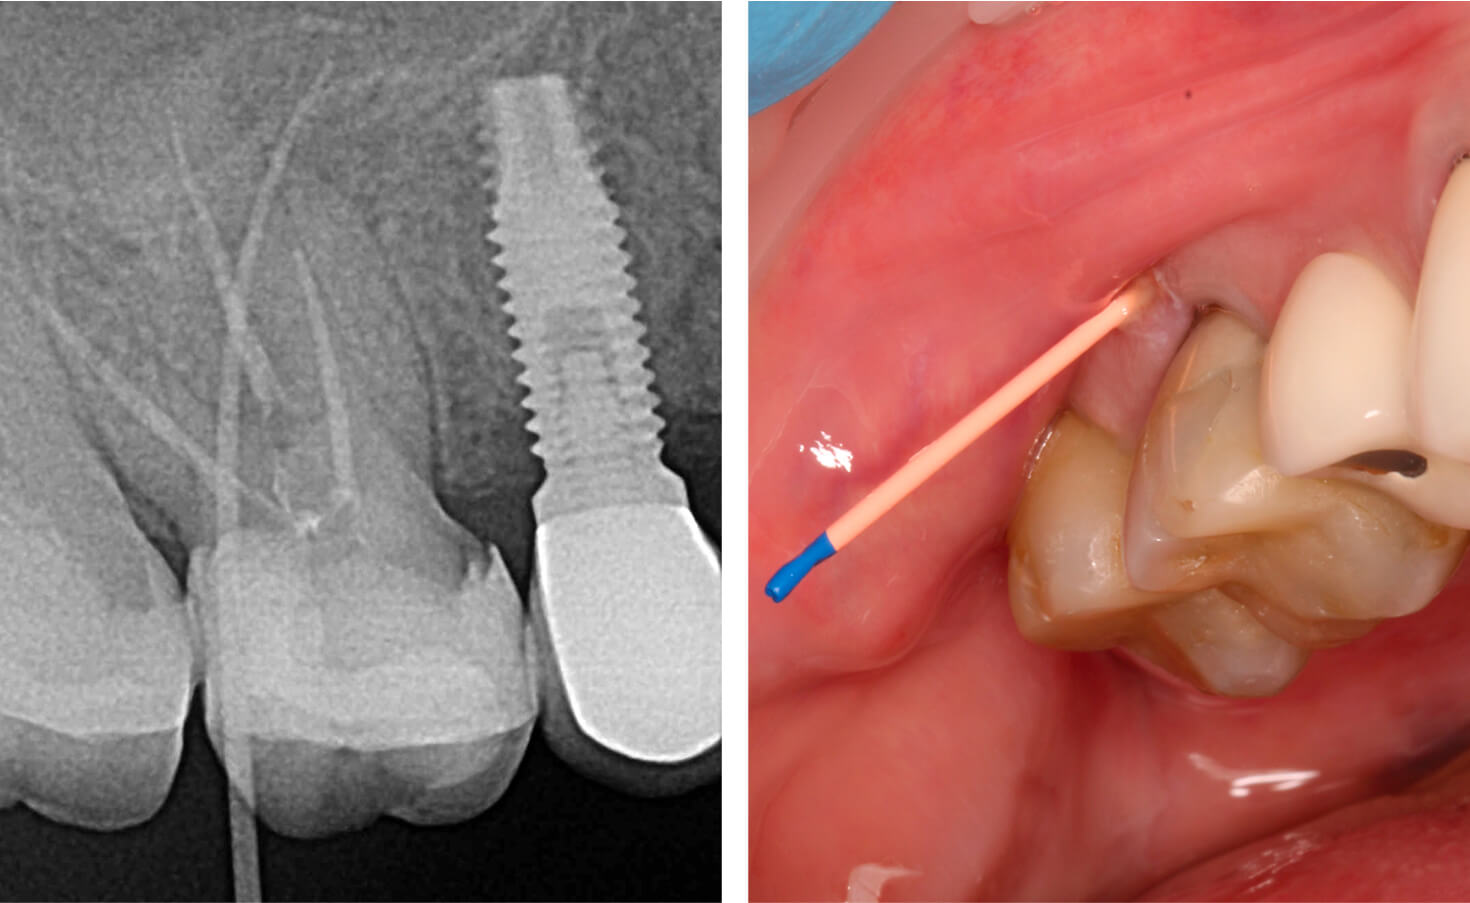

3. By the two-week recall visit, complete closure of the sinus tract was observed, demonstrating favorable resolution of the periradicular inflammation. (Image 6)

4. By the two-week recall visit, complete closure of the sinus tract was observed, demonstrating favorable resolution of the periradicular inflammation. (Image 7,8)

5. By the two-week recall visit, complete closure of the sinus tract was observed, demonstrating favorable resolution of the periradicular inflammation. (Image 9)